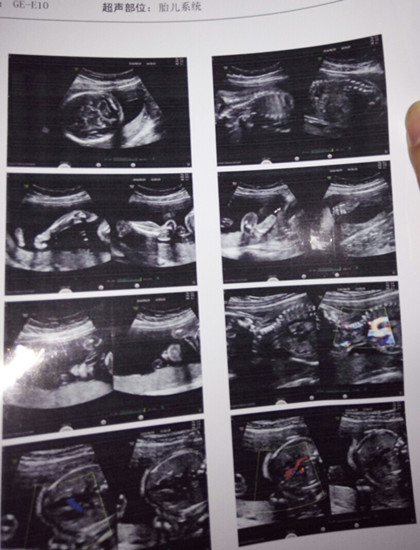

四维彩超又称之为4D彩超,它是在3D彩超的基础上,添加了时间维度参数的功能,也就是大家常说的四维成像技术。通过四维彩超能够很直观,多方位、多角度的观察到胎儿的发育情况,孩子有什么发育畸形,或者是先天性的心脏疾病,都可以及时检查出来。

系统彩超它是一种产科检查中常见的检查技术,系统彩超功能强大,检查范围也比较广泛,包括筛查胎儿畸形(单腔心、无脑儿、严重胸腹壁缺损等),检查羊水量是否充足等。系统彩超是孕期必做的检查项目,它与四维彩超是有区别的。

它是以筛查胎儿畸形为目的的检查,它能够对胎儿的每一个重要器官做出检查,比较系统和全面化,系统彩超出来的图像是断面的。

四维彩超是三维彩超基础上呈现的一个动态的画面,它可以观察到胎儿在母体里的状态,可以立体显示胎儿的面部及器官的发育情况,对胎儿的部分畸形(唇裂、腭裂、骨骼发育异常等)情况可以做到及时发现。